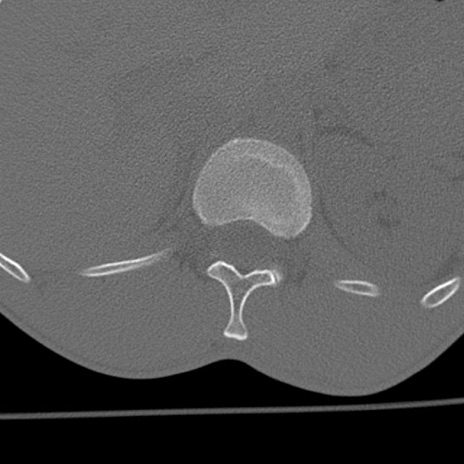

症例3 腰椎CT(横断像)

腰椎CT